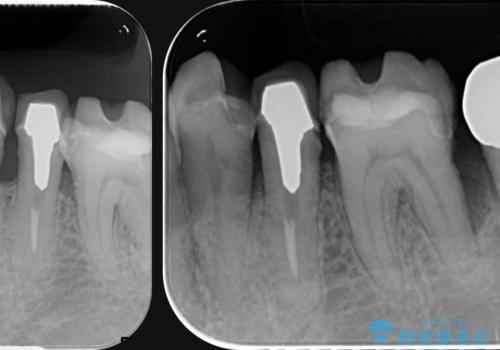

全体的な歯周病検査を行い、多数の残すことのできない抜歯の必要な歯を認めたため、残せる歯に対しての徹底的な歯周病治療、失った歯に対しブリッジ・インプラント治療を全顎的に行っていくこととしました。

長期間にわたる治療後、歯に対する意識も大きく変わりプラークコントロールも非常に良くなりました。

数ヶ月に一度のチェックをしっかりと行い、ブリッジ・インプラントが長期間使用できるようメンテンスを行っていきます。